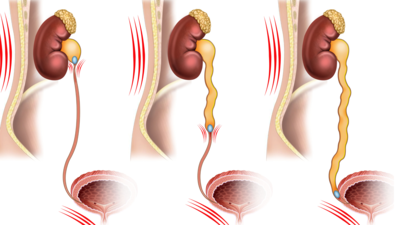

МОЧЕКАМЕННАЯ БОЛЕЗНЬ

Информационный раздел по МКБ